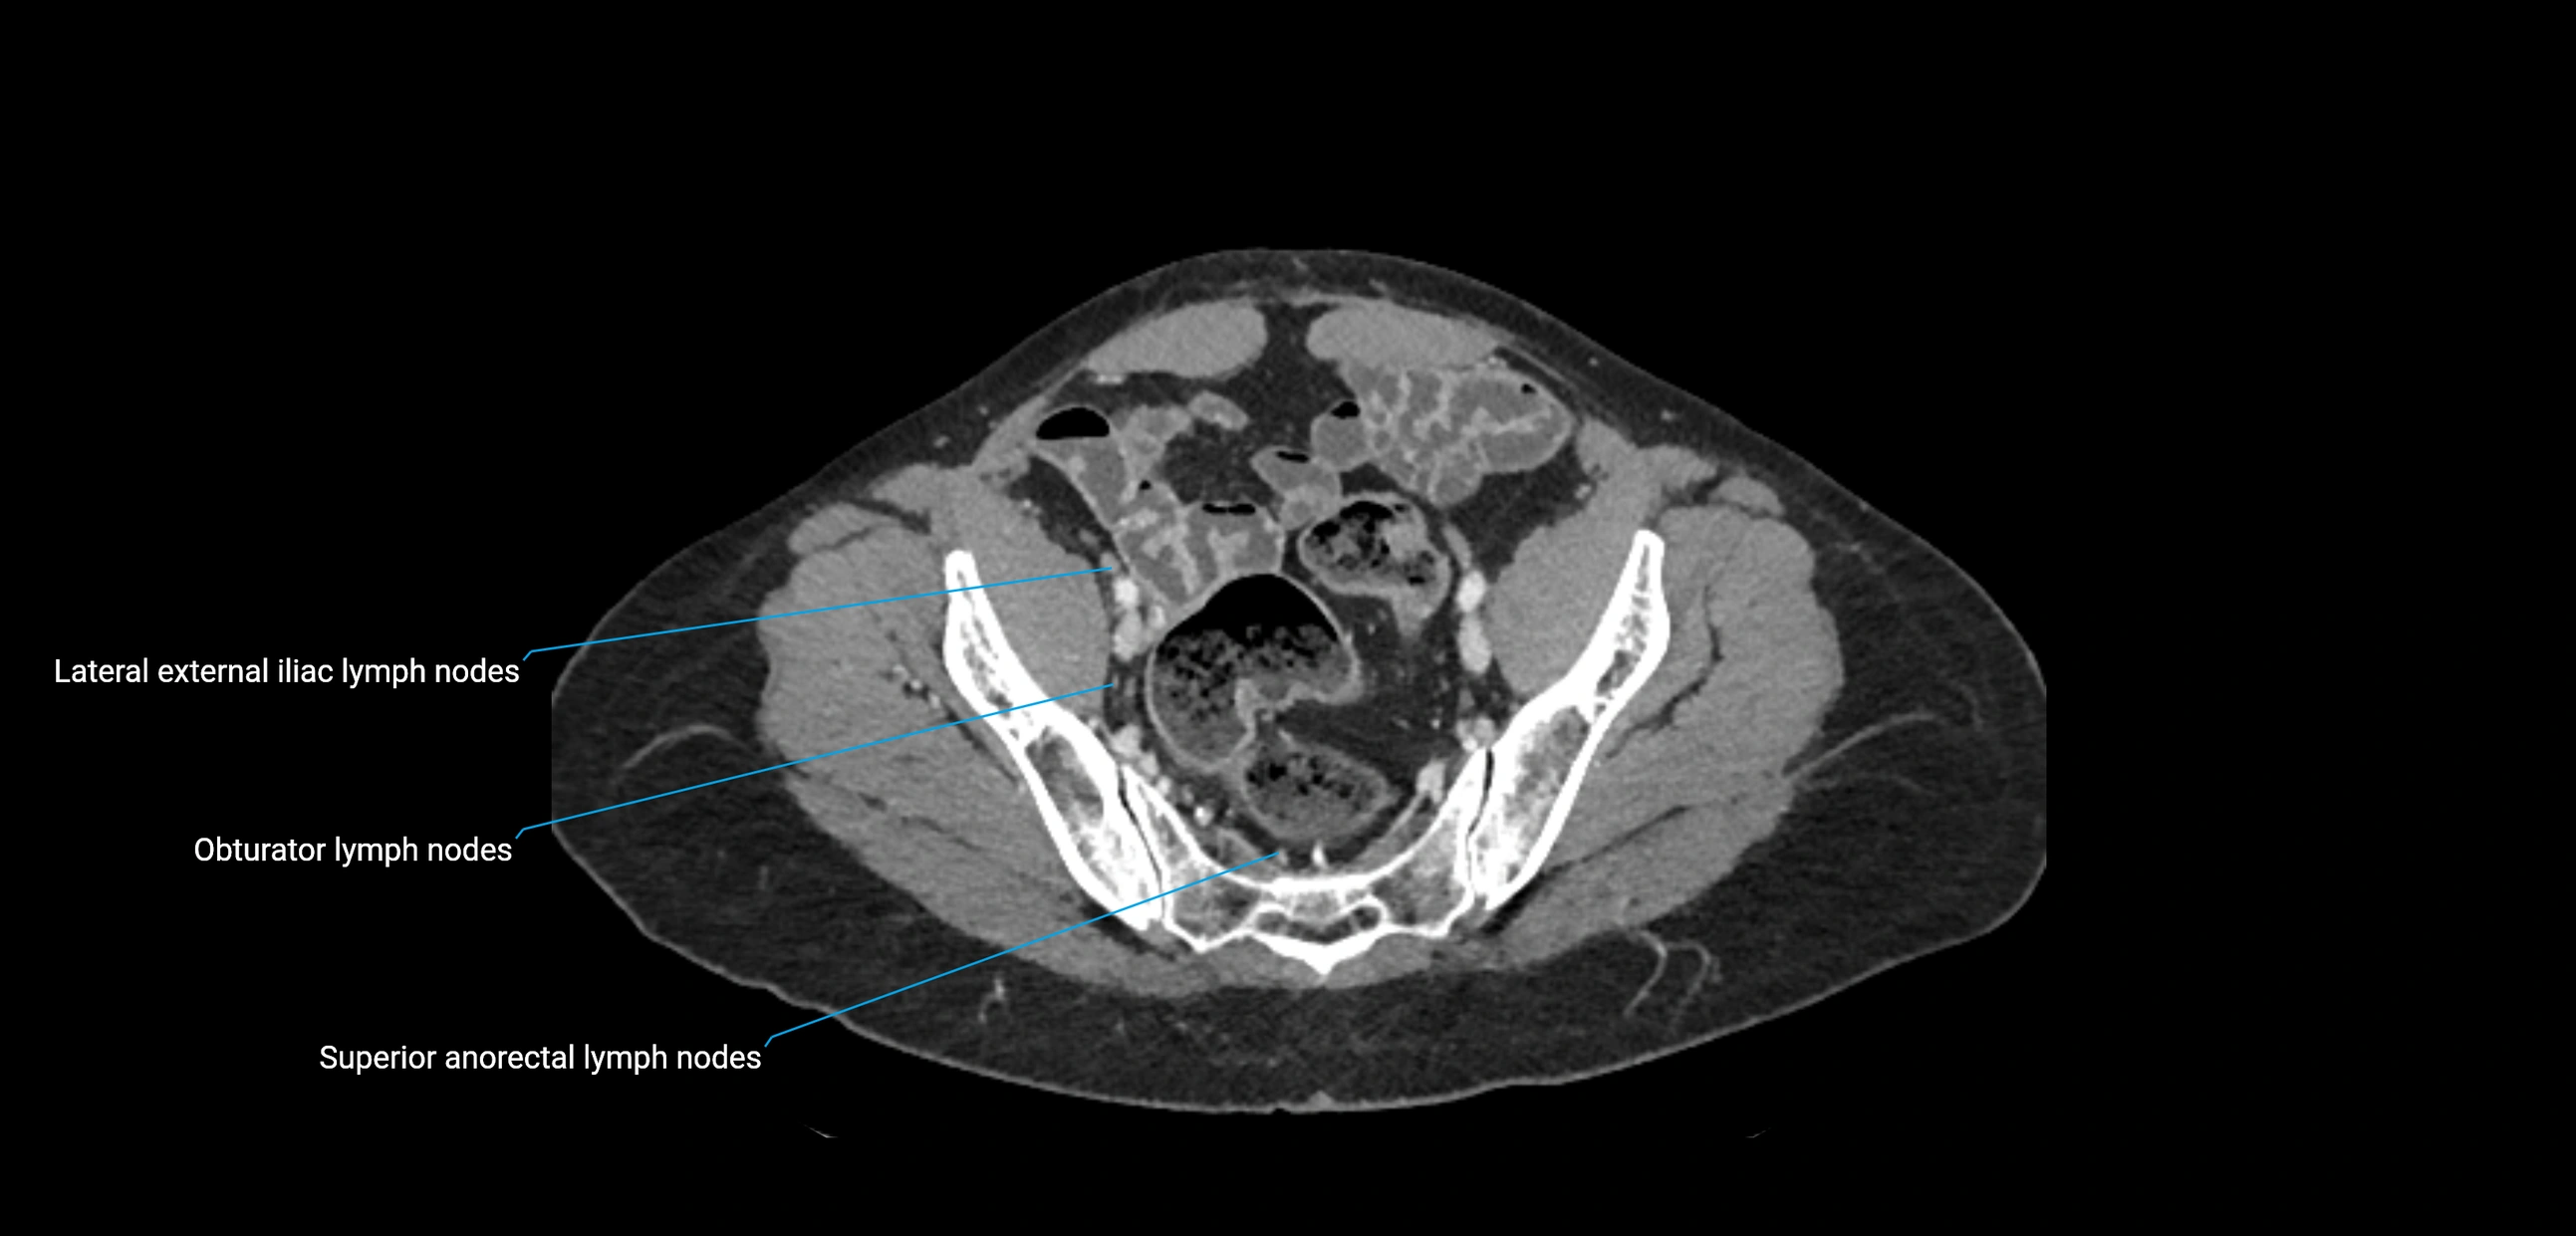

CT Appearance

CT Pre-Contrast:

• Nodes appear as soft-tissue density nodules adjacent to the aorta and IVC

• Calcification may be seen in chronic infections (e.g., tuberculosis)

CT Post-Contrast:

• Normal nodes enhance homogeneously

• Malignant nodes may show heterogeneous enhancement, central necrosis, or conglomerate formation

• Size >1 cm short axis is suspicious, though morphology and distribution are equally important